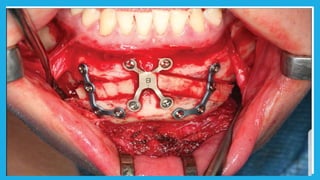

Mandibular orthognathic surgery Itcan be divided into several section:-  Surgery in which the jaw is moved in antrio-posterior direction by an osteotomy either in the ramus or body of the mandible  Surgery to the dentoalveolar area, such as segmental surgery to shift the teeth and alveolus but maintaining the integrity of the lower part of the mandible  Surgery into the chin, moving it in superior , inferior , posterior or anterior direction sometimes accompanied by reshaping

Ramus procedures  Bilateralsagittal split osteotomy(BSSO)